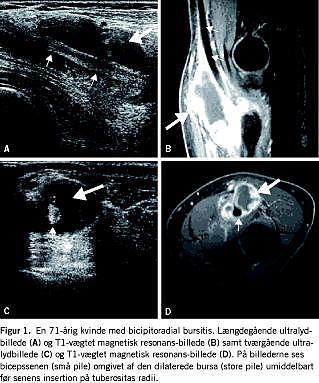

Objektivt fandt man i fossa cubiti en ca. 5 × 6 cm hård, uøm tumorproces, der virkede adhærent til det dybere væv. Relation til muskler og led kunne ikke vurderes. Der var ingen rødme eller hudforandringer. Albuen var frit bevægelig og smertefri ved både aktiv og passiv ekstension og fleksion, og man fandt normal neurologi af hånd og fingre. En røntgenundersøgelse viste normale forhold. Ved en efterfølgende magnetisk resonans (MR)-skanning fandt man en stor cystisk proces, der var beliggende anteriort for den proksimale radius, og igennem hvilken biceps brachii-senen løb (Figur 1, del B og D ). I cirkumferensen og i vægstillede prominenser så man kraftig kontrastopladning. Processen var beliggende tæt op ad collum radii dog uden at gribe over på knoglen eller leddet. Radiologisk var der ingen mistanke om malignitet. MR-billedet, der er vist i Figur 1, er fra en T1-vægtet serie med gadolinium. En efterfølgende ultralydskanning (UL) viste fund, der var i overensstemmelse med MR-skanningens resultat (Figur 1 , del A og C). Ved UL blev der benyttet en 15 MHz lineær transducer. Ved operationen halvanden måned senere fjernede man en cystelignende tumorproces. En histologisk undersøgelse viste synovialis med en svær kronisk inflammation, hvilket er foreneligt med bursitis. Pga. postoperativ infektion blev patienten behandlet med dicillin og aflastning. Efterforløbet var i øvrigt ukompliceret.

Klinisk har patienterne en smertefuld hævelse i fossa cubiti. Typisk ses der smerteforværring ved pronation, hvor bursaen klemmes mellem bicepssenen og tuberositas radii. Den forstørrede bursa vil desuden vanskeliggøre fleksion og ekstension af albuen, og i visse tilfælde kan der opstå mekanisk kompression af n. radialis med nedsat funktion til følge. For yderligere information se [5]. Differentialdiagnoser er bl.a. ganglion og tumor. Karakteristisk for den bicipitoradiale bursa i modsætning til et ganglion er, at bursaen ligger indskudt mellem bicepssenen og dennes insertion på tuberositas radii. Typisk ser man også, at senen ligger invagineret i periferien af bursaen og ikke i dennes center. Tenosynovitis kan udelukkes, idet bicepssenen ikke har nogen seneskede ved insertionen på radius. Ofte kan det være svært at skelne en bicipitoradial fra en interossøs bursitis, specielt hos patienter med en meget stor bursa [2].